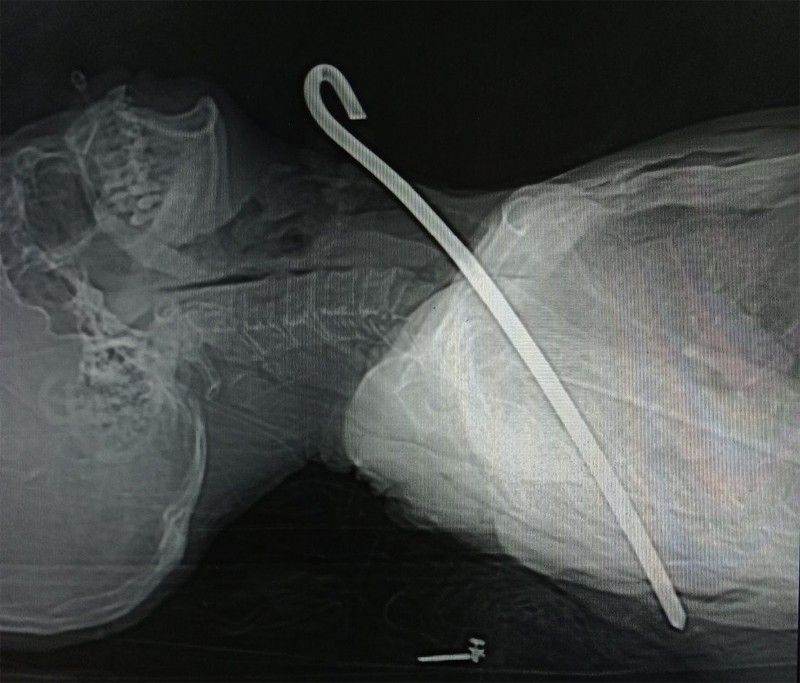

Cứu sống cụ ông bị thanh sắt dài 30 cm đâm vào cổ

Ông được người nhà đưa vào bệnh viện cấp cứu trong tình trạng bị thanh sắt dài 30cm xuyên từ vùng cổ qua phổi phải và trung thất xuống vùng ngực.